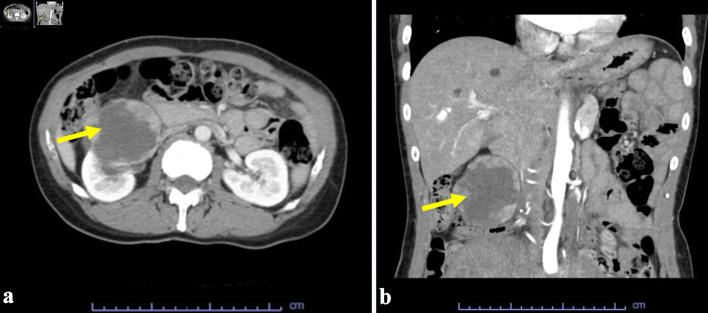

Malignant melanoma (MM) is a tumor that usually occurs in the skin, but this malignant tumor can also develop in extracutaneous tissues, including urogenital tissues. In regard to MM occurring in urogenital tissues, bladder origin is common but renal primary MM is extremely rare. In the Department of Emergency and Urology at Gifu Municipal Hospital, a tumor of the right kidney was detected in a computed tomography scan to determine the cause of severe pain in the lower extremities of a 45-year-old Japanese woman. With the clinical diagnosis of renal cell carcinoma, resection of the right kidney was performed under laparoscopy. The cut surface of the tumor encapsulated by a thick fibrous capsule was dark brown, and the tumor cells with large nuclei, large nucleoli, acidophil cytoplasm, and numerous melanin granules showed papillary, solid, or alveolar growth. Immunohistochemically, the tumor cells were positive for Melan A and human melanoma black 45 (HMG45) but negative for transcription factor E3 (TFE3), transcription factor EB (TFEB), cytokeratin 7 (CK7), carbonic anhydrase 9 (CA9), and AEl/AE3. We conducted careful and detailed examinations, including an association of the patient's medical history, but there were no indications for tumors, particularly MM, in any organs. Therefore, she was ultimately diagnosed with primary kidney MM.